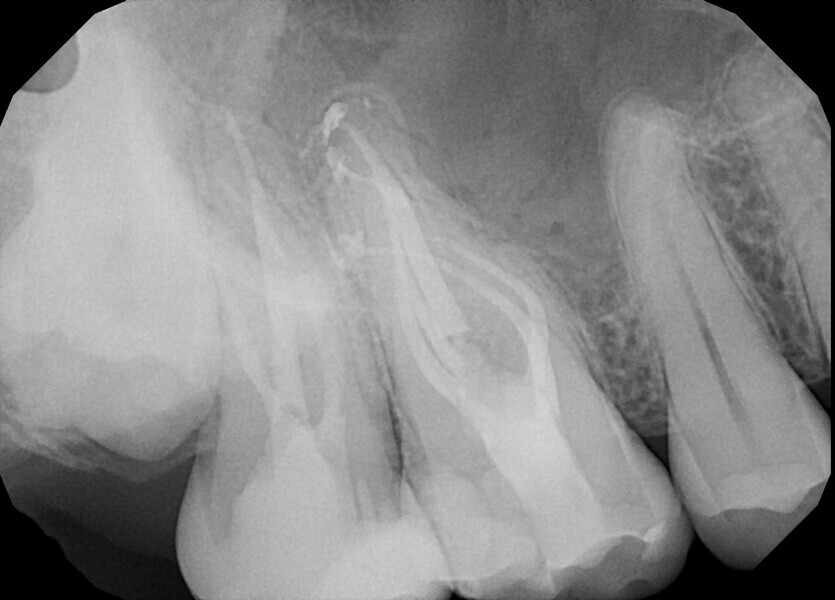

Case 2

A 56-year-old patient was referred to our clinic for endodontic treatment of tooth #15. The initial radiograph showed a complex anatomy with abrupt curvatures (Fig. 19). In such cases, our main goal is to avoid breaking the instrument. The in–out technique is a good choice in these situations too. After isolation, the access cavity was created (Fig. 20). Owing to abrupt curvatures in both canals located, a glide path was achieved with manual ISO #8, 10 and 12 K-files (VDW; Fig. 21). During manual instrumentation, small adjustments to the access cavity were made with an ultrasonic tip (Fig. 22).

After manual glide path preparation, final instrumentation with VDW.ROTATE files was performed using the in–out technique (Fig. 23). After preparation and final irrigation, obturation was performed with the continuous wave compaction technique and 2Seal, a root canal sealer on an epoxy–amine resin basis (VDW; Fig. 24). The final radiograph showed the fully obturated root canal complex (Fig. 25).